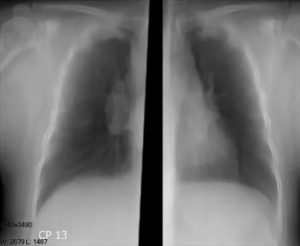

В норме ширина корня легкого соответствует ширине его артериального компонента и в области тела корня равняется 15 мм. Как правило, корни легкого расширяются с обеих сторон, но правый измерить легче, чем левый. Из-за того, что структуры левого легкого на рентгеновском снимке частично прикрыты тенью сердца, левосторонняя патология обнаруживается позднее.

Часто корни легких расширены вследствие увеличения их сосудистого компонента. Это наблюдается при левожелудочковой сердечной недостаточности, когда повышается давление в легочных венах из-за застоя в них крови. В легочной артерии давление может повышаться при заболеваниях легких, например, эмфиземе или ателектазе.

К расширению корня также приводят заболевания бронхиального дерева.

Справочно. Прежде всего, воздухоносный компонент корня расширяется при перибронхитах. При этом инфильтраты вокруг бронхов делают их тень шире, чем она должна быть в норме.

Опасным признаком является полициклически расширенный корень. Как правило, такая патология наблюдается с одной стороны. Полицикличность корню придают лимфатические узлы, которые располагаются по ходу крупных сосудов и бронхов.

Увеличение лимфатических узлов наблюдается чаще всего во время активного туберкулеза, но бывают и более редкие причины: саркоидоз и метастазы злокачественной опухоли.

Внимание. При этом, стоит помнить, что у молодых людей более вероятно наличие туберкулеза, а у пожилых – опухолевого процесса.